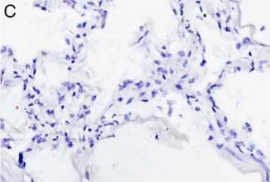

使用 Enzo's AMPIVIEW™ RNA 探针时,SARS-CoV-2 阴性组织无背景染色

|

AMPIVIEW™ SARS-CoV-2 RNA探针 |

AMPIVIEW™ SARS-CoV-2 RNA探针 |

竞品的SARS-CoV-2 RNA探针 |

|

|

|

|

|

"使用其他品牌探针和Enzo AMPIVIEW™ 探针通过ISH检测了一些正常的大脑和胎盘作为SARS-CoV-2 RNA的阴性对照。对比竞品探针的背景(红细胞),使用Enzo探针的背景低。" ——Dr. Nuovo, 俄亥俄州立大学 |